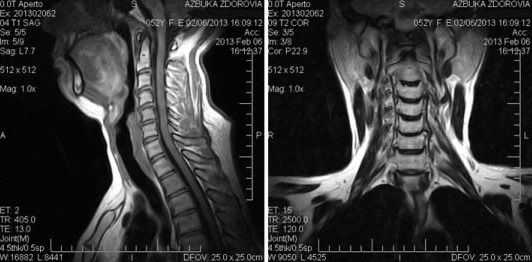

4. МРТ при искусственном шейном межпозвоночном диске:

• Протезы, состоящие из нетитановых сплавов (сплавы кобальта/хрома/молибдена в протезах РСМ и ProDisc-C), приводят к появлению на МР-томограммах артефактов магнитной восприимчивости, которые порой не дают адекватно оценить состояние как уровня вмешательства, так и смежных уровней

• Титановые импланты и полиэтилен (Bryan disc или Prestige LP) обеспечивают удовлетворительную визуализацию как смежных, так и оперированного уровней

• МРТ позволяет оценить состояние костной ткани тел позвонков, диагностировать переломы и дегенеративные изменения межпозвонковых дисков и дугоотростчатых суставов смежных уровней

• МРТ в послеоперационном периоде может быть показана при сохраняющемся болевом синдроме для оценки адекватности выполненной декомпрессии или диагностики миелопатии

(Слева) На сагиттальный срез, Т2-ВИ: грыжа диска С5-С6. Согласно современным литературным данным, ТЗШД-это вариант хирургического лечения шейной миелопатии у пациентов молодого возраста с центральными грыжами диска без выраженных дегенеративных изменений диска и дугоотростчатых суставов на уровне этого сегмента.